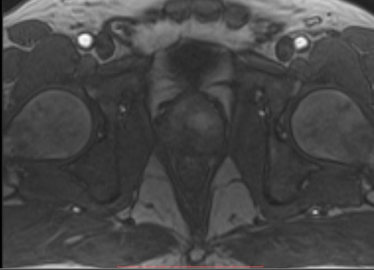

МР-диагностика рака предстательной железы (мультипараметрическая МРТ)